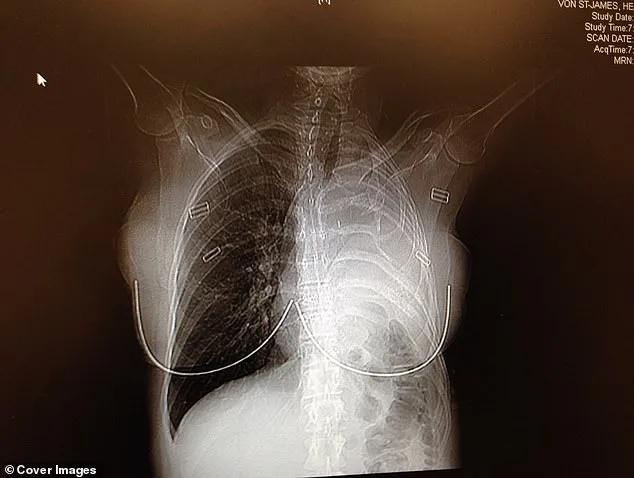

Her doctor's initial tests revealed a tumor in the pleura, the thin membrane lining the lungs and chest cavity. A CT scan confirmed the diagnosis: malignant pleural mesothelioma, a rare and aggressive cancer with a grim prognosis. "I didn't know what mesothelioma was," she admitted. "The doctor asked if I or anyone in my family had ever worked with asbestos. I looked at my husband, and he looked at me. He said, 'Oh, this is bad.'" Without immediate intervention—surgery, chemotherapy, or radiation—her survival outlook was bleak. At most, she had 15 months to live. "It was disbelief," she said. "How could this be happening?"

She and her husband flew to Boston to see a specialist who performed a radical surgery. In February 2006, doctors removed her left lung, a rib, the lining of her heart, and part of her diaphragm, replacing them with surgical Gore-Tex. The tumor was excised with clean margins. No visible cancer remained. "My mind was spinning and I couldn't breathe," Von St James said. "I started to have a panic attack in that room while they were explaining what mesothelioma was. I began crying and had to leave the room." It was the hardest day of her life. She felt incredibly alone and scared.

In February 2006, doctors removed her left lung, the rib above it, the lining of her heart, and part of her diaphragm. In their place, they used surgical Gore-Tex—the same material used in waterproof clothing—to rebuild parts of her chest. The surgery was a success. Surgeons had excised the tumor with perfect margins, leaving no visible cancer behind. As a precaution, to make sure they removed every bit of cancer, doctors infused warm drugs directly into her chest cavity, rocking her back and forth for an hour to circulate the medicine and kill any remaining cancer cells. "Patients call it the 'shake and bake,'" Von St James said. She endured four rounds of chemotherapy and 30 sessions of radiation. "People say once you survive cancer, everything should be great," she said. "But there are a lot of ongoing physical things that happen after surgeries."